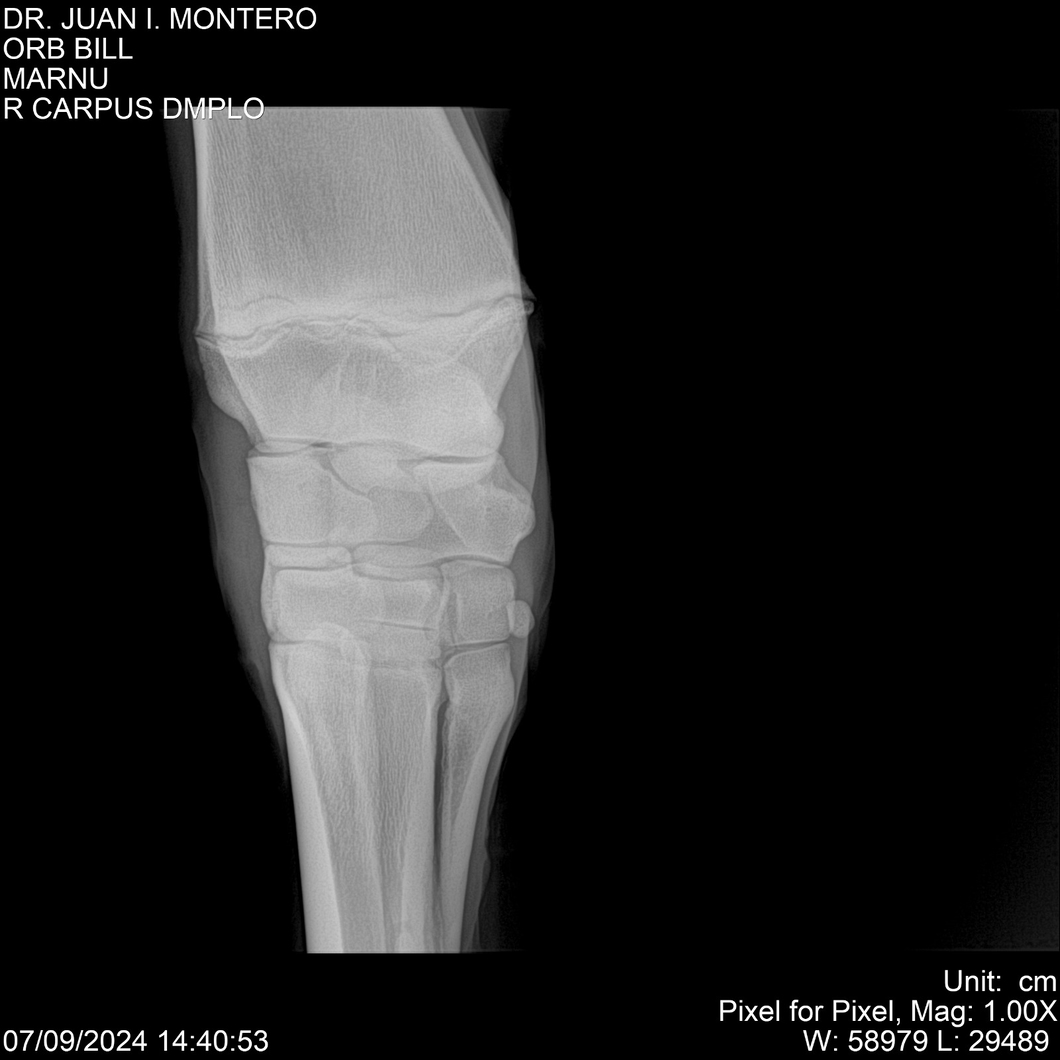

LOTE 7, ORB BILL 🔥 🔥 🔥 Lote Anterior Volver al remate Lote Siguiente Ficha Contacto Montevideo - Ficha del Lote Identificador: #282523 Categoría: Yeguarizos Montevideo - 83 Visualizaciones ClicData Contacto Empresa: Abelenda N. R., Walter Hugo Nombre*: Teléfono* : E-mail* : Mensaje Enviar Registrese gratis Este contenido Exclusivo está disponible sólo para usuarios registrados Ingresar